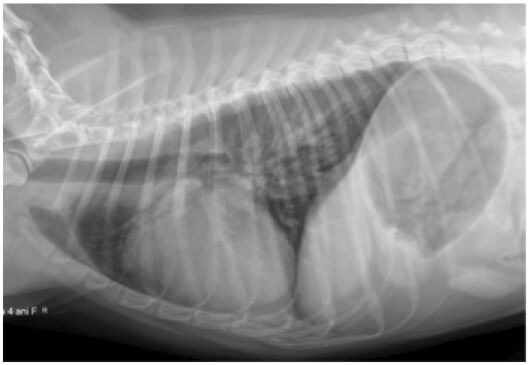

Boala determinata de viermii cardiaci reprezinta probabil cea mai comuna cauza a cor pulmonale la caini. Aceasta inseamna o insuficienta a ventriculului drept datorita hipertensiunii pulmonare secundara afectarii vaselor de sange pulmonare.